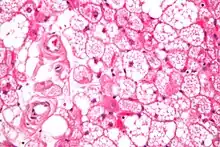

| Micrograph of a hibernoma. H&E stain. | |

The tumors histologically resemble brown fat. There are four histologic types recognized, but one is the most frequently seen (typical). There is a background of rich vascularity.

- Lobular type: Variable degrees of differentiation of uniform, round to oval cells with granular eosinophilic cells with prominent borders, alternating with coarsely multivacuolated fat cells (pale cells). There are usually small centrally placed nuclei without pleomorphism. The cells have large cytoplasmic lipid droplets interspersed throughout.[3][4]